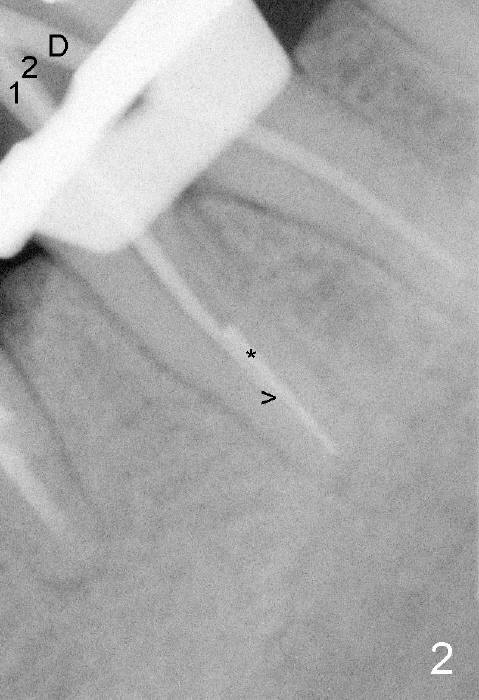

插入主牙胶尖(近中颊侧30/.04,近中舌侧30/.06,远中40/.04)后,拍摄根尖片(图二),近中牙胶尖(1,2)部分与断针(*)重叠,箭头指向牙胶尖下端,D是远中牙胶尖。然后准备根管充填,用纸尖吸干根管时,断针看得很清楚,接着使用Piezo超声波加上diamond tip在扩大断针周围扩大根管,用hand files能拨动断针,但是不能让断针上下移动,虽然我们有微型钳子,但是估计头还是太大,插不进根管里。最后还是草率收兵:根管充填,近中颊侧,远中根管使用主牙胶尖外,还插入多根副牙胶尖,而近中舌侧根管就使用一个主牙胶尖(图三):*:断针,箭头:充填下端。最后做树脂buildup,现在术后一个多月,病人好像没事,不想近期回诊所做下一步治疗。